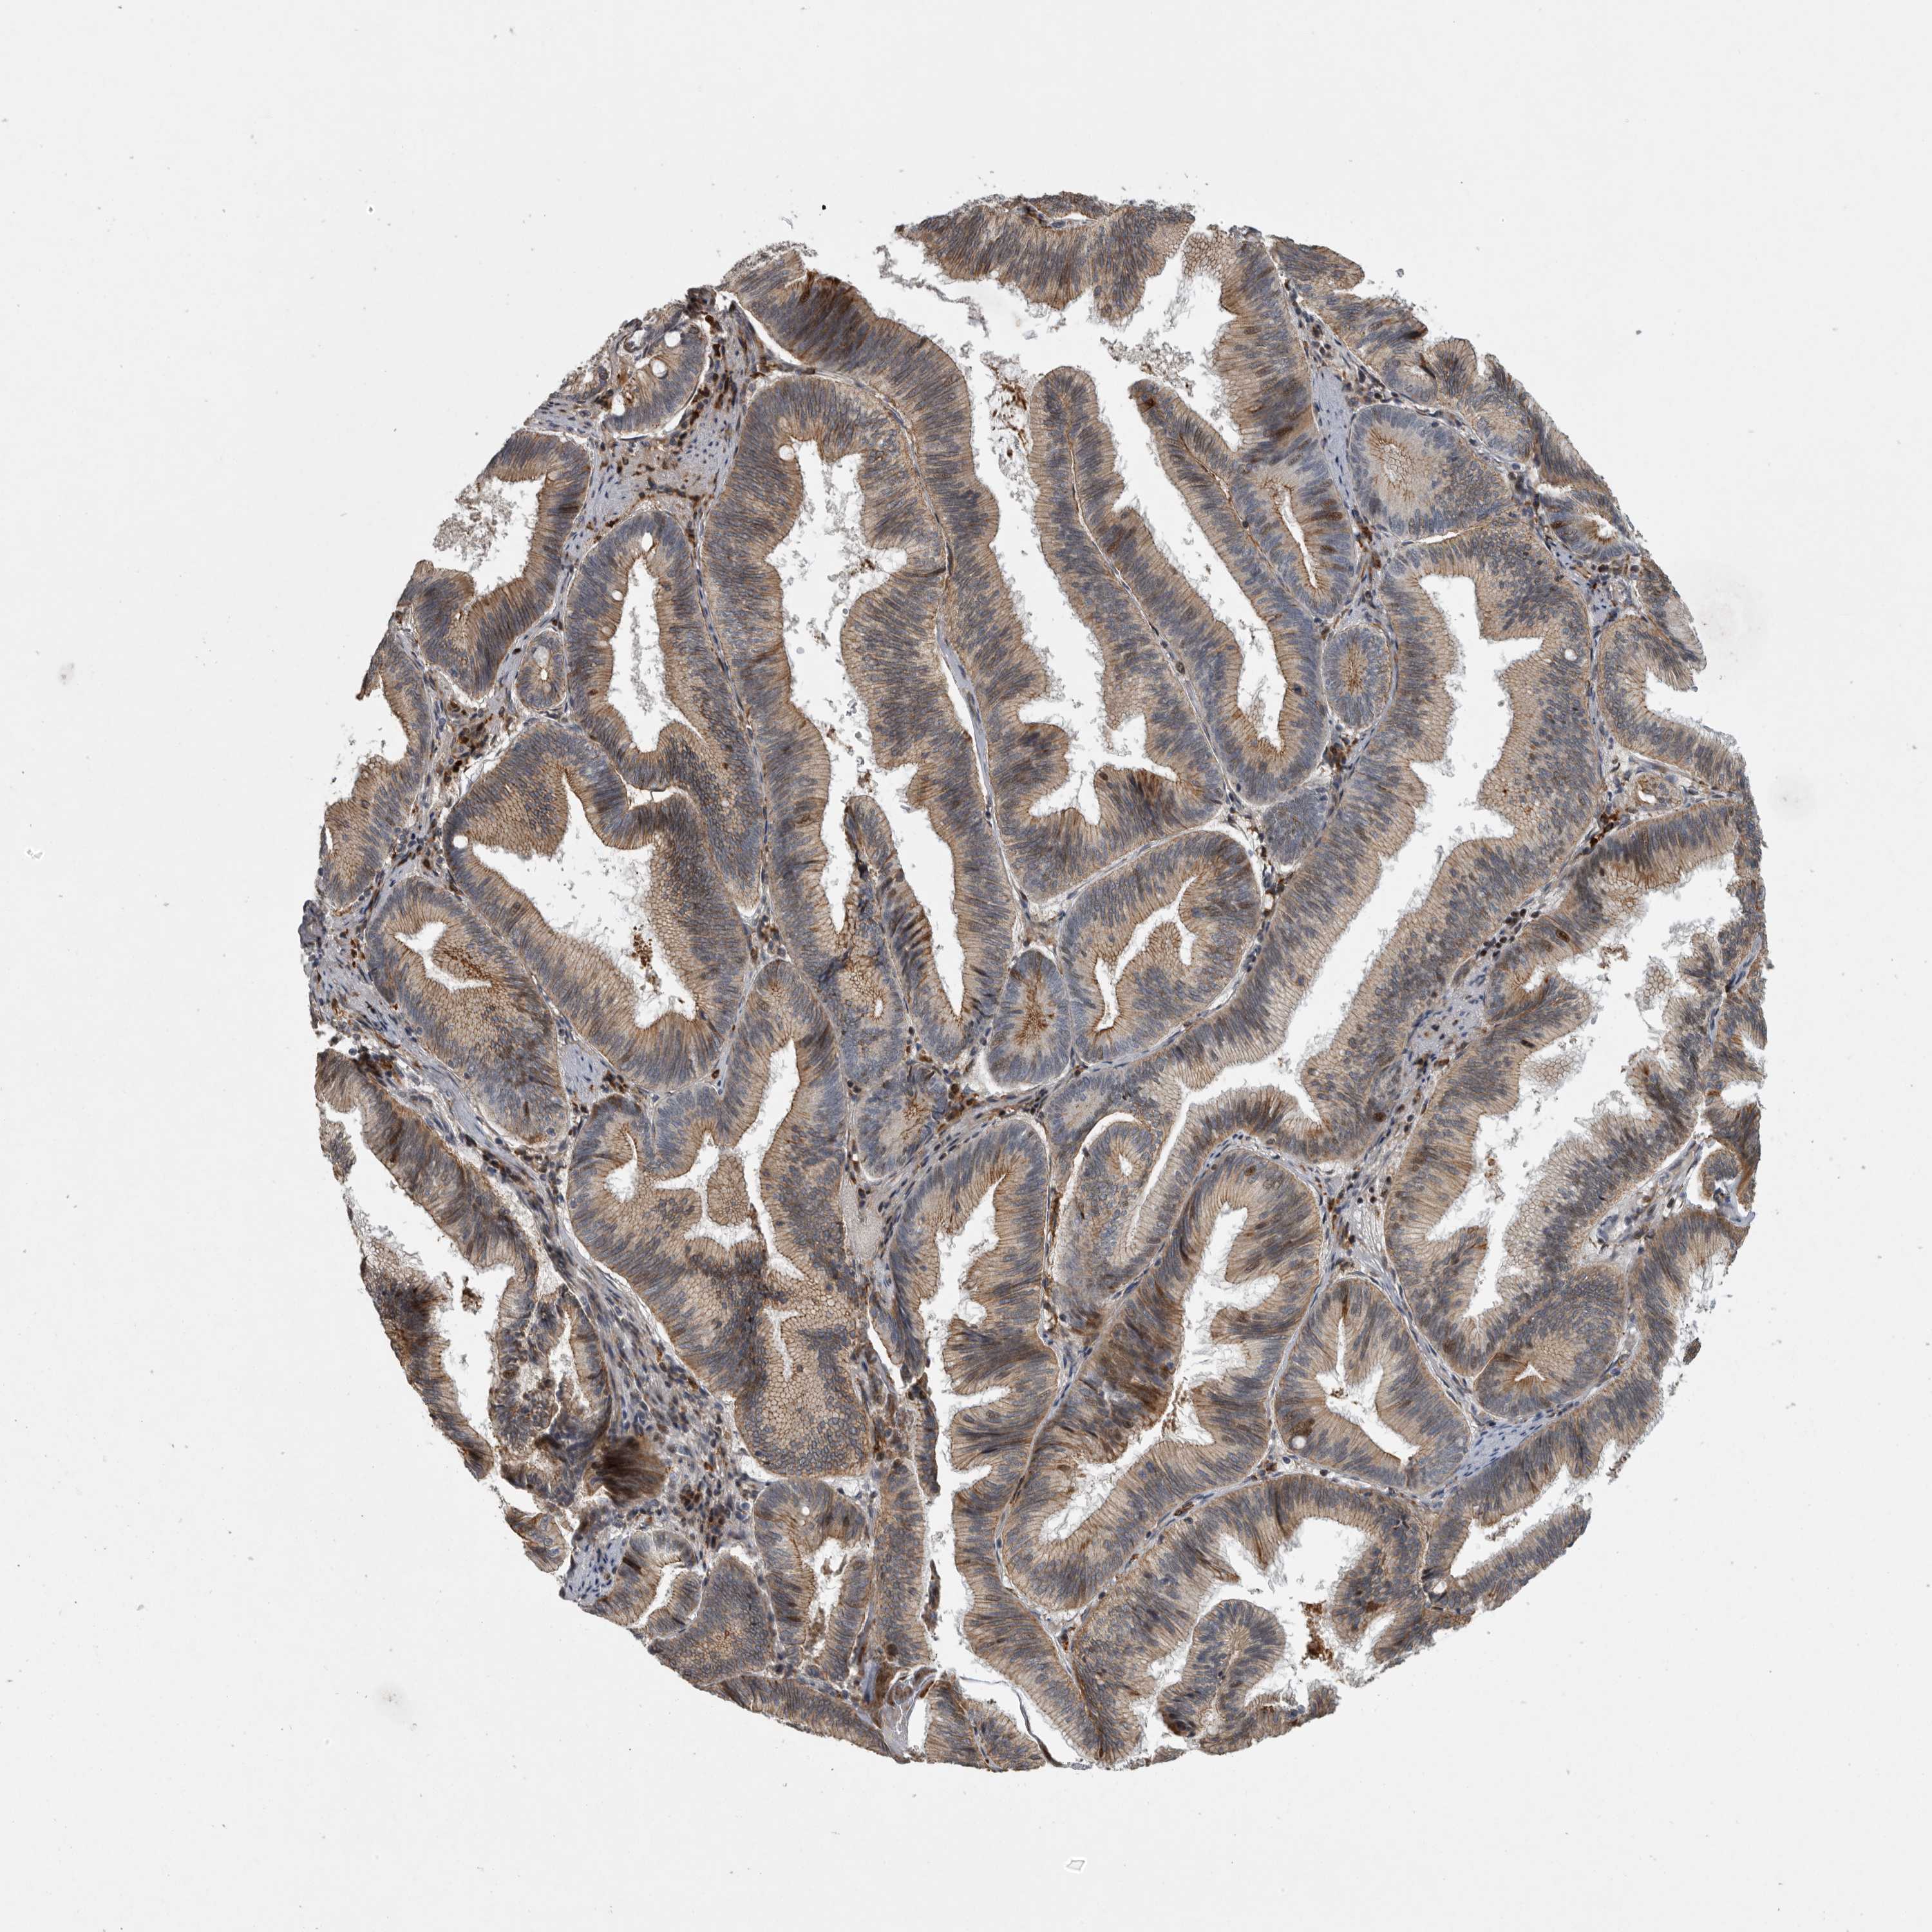

PANCREATIC CANCER - Protein expressioni

A mouse-over function shows sample information and annotation data. Click on an image to view it in a full screen mode. Samples can be filtered based on level of antibody staining by selecting one or several of the following categories: high, medium, low and not detected. The assay and annotation is described here.

Note that samples used for immunohistochemistry by the Human Protein Atlas do not correspond to samples in the TCGA dataset.

Antibody stainingi

Antibody staining in the annotated cell types in the current human tissue is reported as not detected, low, medium, or high, based on conventional immunohistochemistry profiling in selected tissues. This score is based on the combination of the staining intensity and fraction of stained cells.

Each image is clickable and will lead to virtual microscopy that enables deeper exploration of all samples and also displays staining intensity scores, fraction scores and subcellular localization as well as patient and tissue information for each sample.

Antibody HPA020255

Antibody HPA026686

Antibody CAB013512

Adenocarcinoma, NOS

Adenocarcinoma, metastatic, NOS